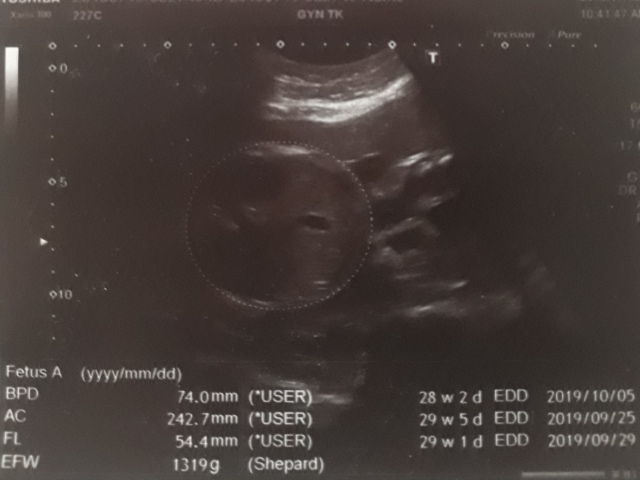

29週又3天↓

近七次產檢資料統計(BPD量出來竟然比兩星期前還小,可能有錯誤)↓

| 2019年07月15日 | 74.0mm (-1%) | 242.7mm (16%) | 54.4mm (8%) | 1319g (20%) | 133 |

| BPD:胎兒頭骨橫徑 AC:胎兒腹圍的長度 FL:胎兒大腿骨的長度 EFW:胎兒的體重 括弧內百分比為較上次產檢的成長比例 | |||||